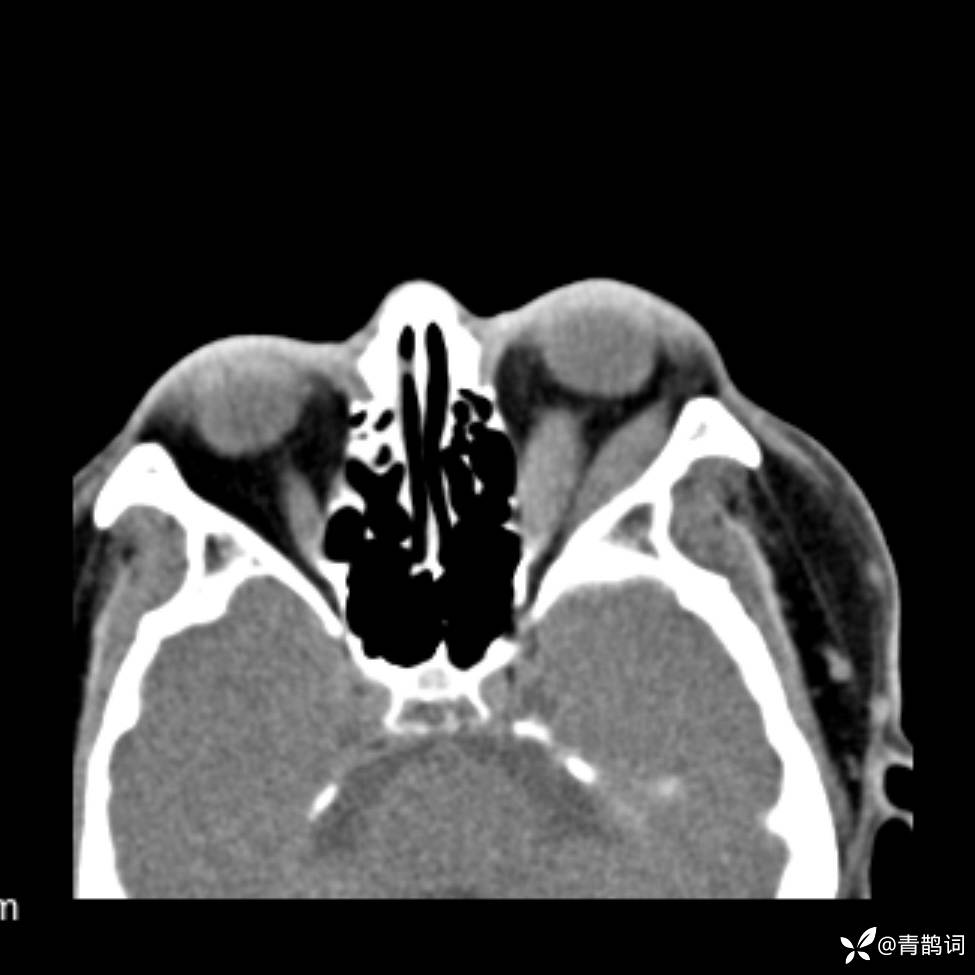

患者年龄:30岁。

患者性别:男。

简要病史:左颜面部肿胀2年,反复咳嗽咳痰,逐渐加重。

辅助检查

结合病史及影像学表现,期待评论区各位老师各抒己见~